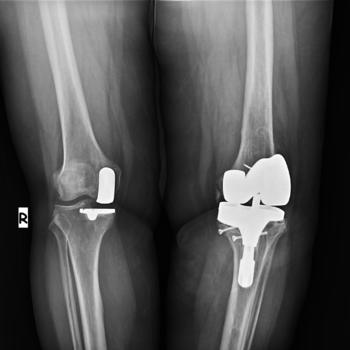

What is partial knee replacement?

Partial knee replacement, also called a unicondylar knee replacement, is a surgery that may be considered for treatment of osteoarthritis of the knee joint if the arthritis in the knee is confined to a limited area. Partial knee replacements are an alternative to Total Knee Replacement and can be recommended for patients who are:

Several studies have demonstrated the advantages of this treatment option over the more conventional Total Knee Replacement. These include: a smaller scar, less pain, a potentially shorter hospital stay, a faster rehab and recovery time, and possibly a greater range of motion when compared to standard total knee procedures. In addition, because more of the knee remains untouched, patients often report that the knee feels more normal to them.

Partial Knee replacement surgery details

The surgery takes about one and a half hours. An incision is made over the knee and the worn out cartilage is exposed. The rough edges of the end of the femur (a bone that goes from the hip to the knee) and top of the tibia (a bone that goes from the knee to the ankle) are cut flat, cleaned, and then the unicompartmental device is cemented in place. The devices used at our partner hospitals are western brand ones such as Biomet Oxford II.

What is Knee Replacement Surgery?

One of the most important orthopedic surgical advances of the twentieth century, knee replacement was first performed in 1968. Improvements in surgical materials and techniques since then have greatly increased its effectiveness. Approximately 300,000 knee replacements are performed each year in the United States alone, making it one of the most common surgeries.The results are impressive. The procedure itself takes approximately 1-2 hours. Your orthopaedic surgeon will remove the damaged cartilage and bone and then position the new metal and plastic joint surfaces to restore the alignment and function of your knee. Special surgical instruments are used to precisely measure an optimal fit of the implant.

How Long Will the Knee Implant Last?

The longevity of the implant depends on many factors such as the patient’s weight, the patient’s activity level, and the presence or absence of disease in other joints of the lower extremities. Implants can last ten to fifteen years and even longer. New techniques allow for an implant to be removed and replaced, but our goal is to be able to implant a prosthesis that will last the patient a lifetime without revision.

Knee Replacement Surgery Results

Results are impressive and gratifying to both the patient and the surgeon. Most patients are pain-free and able to bend their knees from 90° to 100°, resuming daily activities without restriction. The remarkable results of total knee replacement are due to patient determination, the surgeon’s skill, and the bioengineers’ well-designed implants and instruments. Continued advances in the field can be expected to result in continuing success in the future.